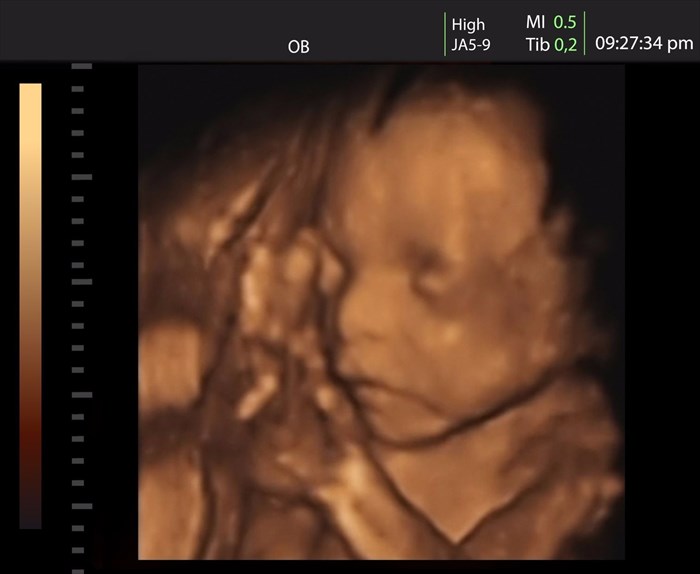

• Three-dimensional ultrasound images (3D ultrasound): Two-dimensional visuals can also be projected onto those of three-dimensional representation. Tissue is scanned in cross sections from numerous angles. Data is then reconstructed into a three-dimensional image. A 3D scan can help to provide a more comprehensive visual, which can be more realistic. A common use for such a visual is during a woman’s pregnancy when viewing and monitoring a developing foetus (unborn baby).

Example of a three-dimensional (3-D) ultrasound scan showing an unborn baby in a woman's uterus (womb).